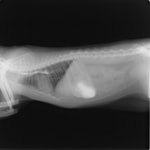

4歳 アメリカンショートヘアー

主訴:3日前から嘔吐が続き、食欲も落ちてきたのこと。

対症療法(症状に対する治療)に反応しないため、精査を実施。

一般血液検査:問題なし

単純レントゲン検査:胃内ガス陰影・腸内ガスが少量認められる。

嘔吐が改善しないため、消化管バリウム造影検査を実施。

以下、

消化管バリウム造影レントゲン

バリウム造影3時間経過するも、胃内からバリウム排泄なく同日内視鏡検査を実施。

内視鏡検査結果:内視鏡下にて、バスケット鉗子を用いて摘出。

症例は、机の上に置いていたピスタチオのお菓子を誤飲していました。その後の経過は良好です。本症例は、内視鏡下にて摘出ができましたが、球状・立体などの大きな異物は、腸の途中で詰まりやすく、内視鏡下での摘出が困難な場合もあります。その際は、開腹下にて腸内の異物を摘出しなくてはなりません。動物たちは、思わぬ物を誤飲することがあります。お留守番時・就寝時は、誤飲をしやすい時間帯ですので注意しましょう。